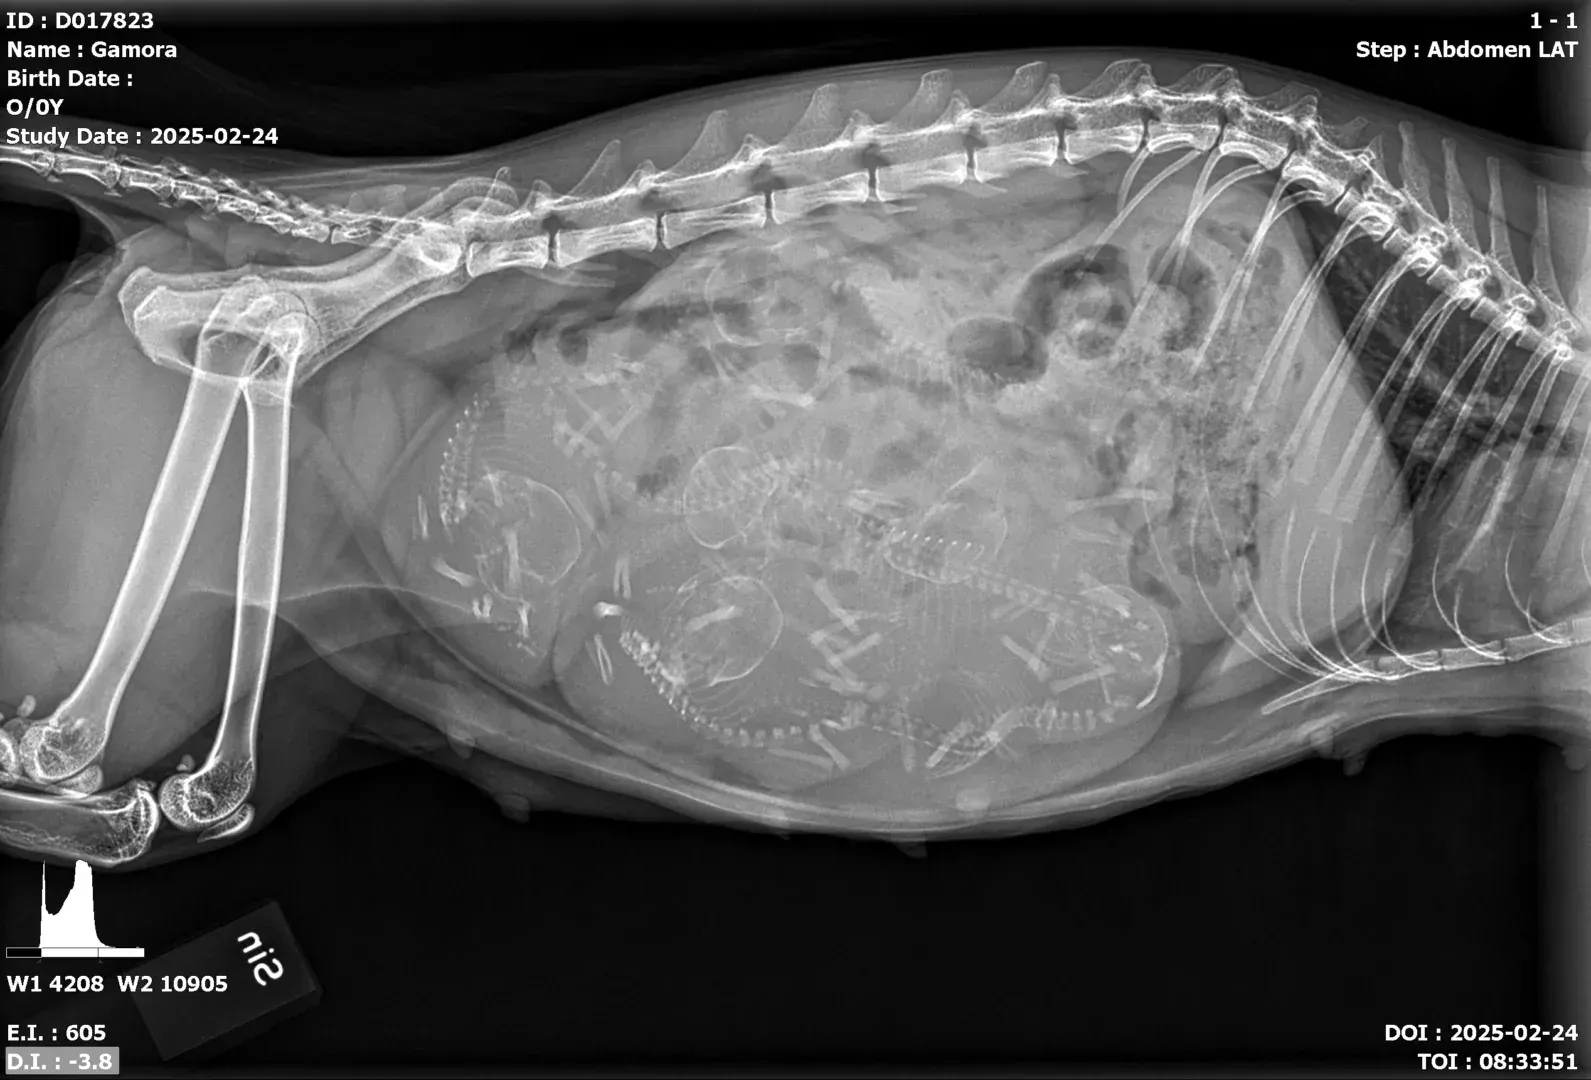

Gamora har blivit mamma! Läs om hennes nyfödda kattungar och se de första bilderna.

Följ Gamoras resa genom graviditeten och förberedelserna inför hennes fjärde kull kattungar i mars.